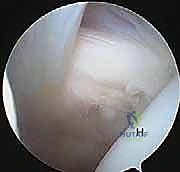

2. إحداث الثقوب (Portals) واستكشاف المفصل

يقوم الدكتور هطيف بعمل 3 إلى 4 ثقوب صغيرة جداً حول الكتف. يُدخل كاميرا المنظار (Arthroscope) لعمل جولة استكشافية شاملة لداخل المفصل، وتقييم الغضاريف، أوتار الكفة المد